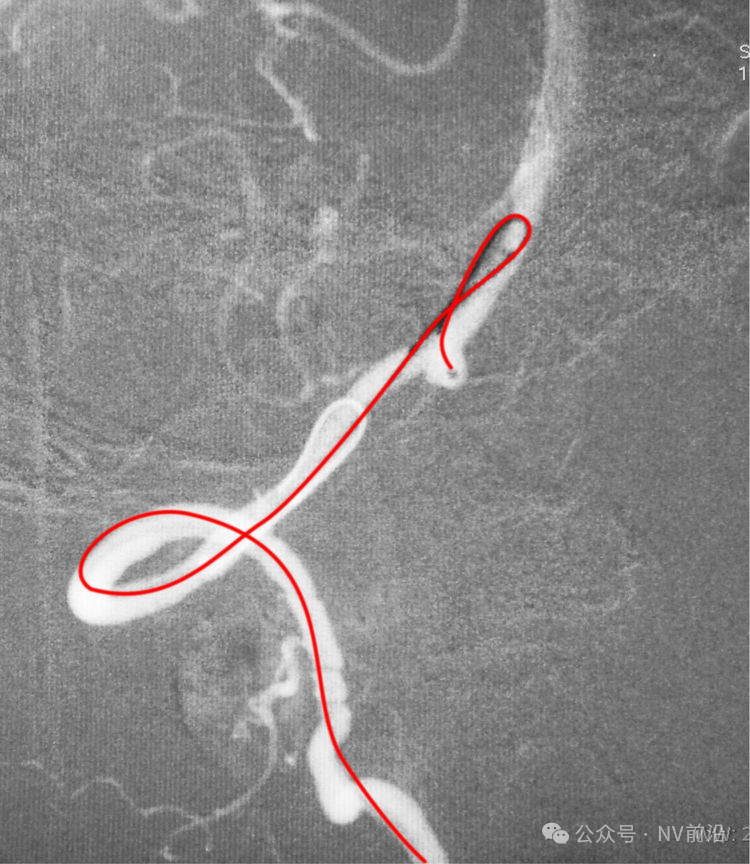

Echelon 10微导管头无论塑成C形还是S形,均无法稳定于动脉瘤腔内,遂使用回马枪技术,使微导管成襻通过,管头折返入瘤腔。

跨瘤颈释放Solitaire 4×20支架(蓝线),压住微导管(红线),在支架保护下经返折的微导管送入弹簧圈填塞瘤腔。